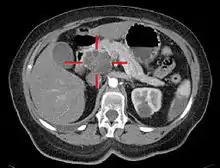

تُستخدم تقنيات التصوير الطبية كالتصوير المقطعي المحوسب والتنظير بالموجات فوق الصوتية في التشخيص والمساعدة في اتخاذ قرار إذا كان الورم يُمكن إزالته جراحيًا (قابلية استئصاله)[64]، ففي تباين التصوير المقطعي المحوسب يُظهر سرطان البنكرياس زيادة تدريجية في امتصاص مادة التباين الشعاعي، وذلك يختلف عن الإزالة السريعة التي تُرى في حالة البنكرياس الطبيعي، أو البطيئة التي تُرى في حالة التهاب البنكرياس المزمن.[67] يمكن أيضًا استخدام التصوير بالرنين المغنطيسي والتصوير المقطعي بالإصدار البوزيتروني[68] وكذلك يُمكن أن يكون تصوير البنكرياس والأوعية الصفراوية بالرنين المغناطيسي مفيدًا في بعض الحالات[65]، يُعد تخطيط الصدى البطني أقل حساسية وربما يفقد الأورام الصغيرة لكنه يُمكنه التعرُّف على السرطانات التي تنتشر إلى الكبد وتتكون من سائل في التجويف الصفاقي(استسقاء بطني)[64]، لذلك يمكن استخدامه للفحص الأولي السريع والرخيص قبل التقنيات الأخرى.[69]

.jpg.webp)